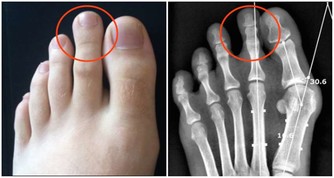

3、排尿障礙。前列腺癌患者會出現排尿困難、尿流變細或尿流分叉、尿程延長、尿頻、尿急、尿痛、尿不盡感等症狀,嚴重時還可發生尿滴瀝及尿瀦留。

據調查顯示,百分之八十的病人有癌灶引起進行性排尿困難,尿流變細或尿流偏歪,或尿流分叉、尿程延長、尿頻、尿急、尿痛、尿意不盡感等,嚴重時尿滴瀝及發生尿瀦留。這是晚期前列腺癌的常見症狀之一。